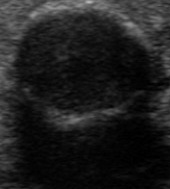

Coarse calcification

The next typical hyperechogenic figure is the coarse calcification. The shape is linear or curved or might be granular. In smaller foci it might seem to be round. It ranges from 1 mm to several cm and presents a dorsal acoustic shadow. The latter is the ultrasound hallmark of coarse calcification. Often, we did not find the calcified focus and only the dorsal acoustic shadow proves the existence of calcification. According to recent studies, macrocalcifications within a nodule, if combined with microcalcifications, confer the same malignancy risk as microcalcifications alone (18,21) refers the current guideline of the ATA (5), while just the opposite states the newest guideline of ETA: "microcalcifications are highly suggestive of malignancy, in particular when associated with macrocalcifications" (1). The presence of intranodular (central) macrocalcification alone is not consistently associated with thyroid cancer (23). Calcification represents perhaps a possible pathologic evolution of some thyroid lesions (24).

We have to mention the eggshell-calcification or peripheral rim calcification. This corresponds to calcification of the capsule of a lesion. There are conflicting studies whether this feature would increase the risk of malignancy. Certainly, if it does, then more in a statistical than in a practical sense. However, a nodule that has interrupted peripheral calcifications, in association with a soft tissue rim outside the calcification, has been reported highly likely to be malignant, and the associated pathology may demonstrate tumor invasion in the area of disrupted calcification (25-27). The issue is that a direct tumor spread is only rarely unequivocal on ultrasound. In the TIRADS of the American College of Radiology macrocalcifications is worth 1 point, while peripheral (rim) calcification is worth 2 points (see Table 2 of ref. 4), no type of macrocalcifications is included in the scoring system of the latest European TIRADS (1).